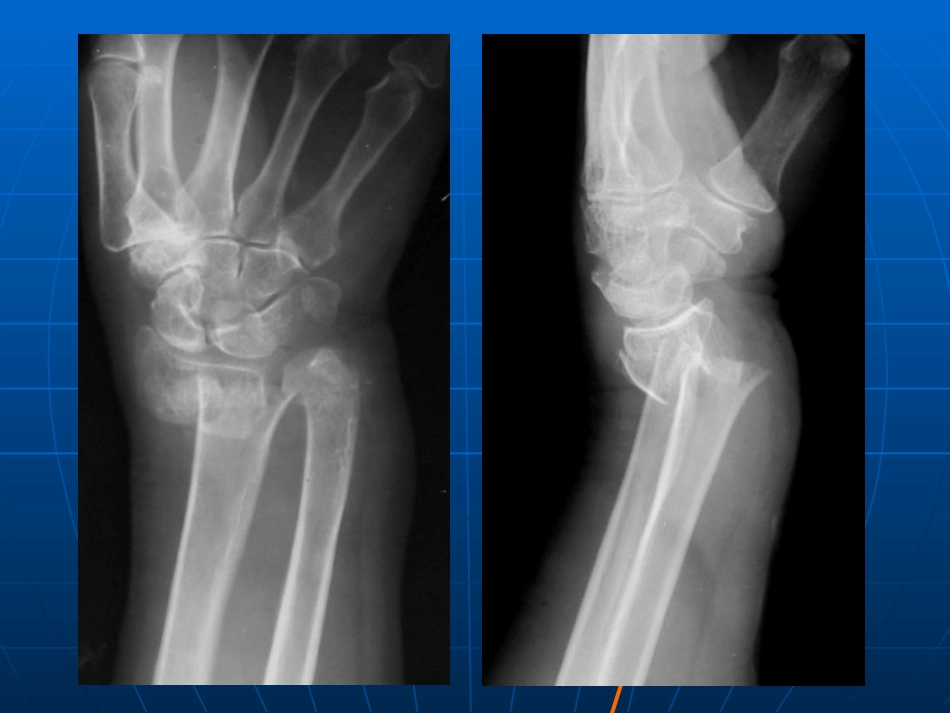

医学影像学作业题医学影像学作业题案例一案例一男,男,35y35y,外伤后,外伤后11小时,右手肿胀伴活小时,右手肿胀伴活动受限。动受限。案例二案例二病史:患者,女,病史:患者,女,2727岁,发热岁,发热22天。天。案例三案例三患者,男性,患者,男性,1717岁,消瘦、食欲减退伴咳岁,消瘦、食欲减退伴咳嗽、胸痛数月,偶有咯血。嗽、胸痛数月,偶有咯血。病例四病例四患者,女性,患者,女性,4646岁,头痛、头晕,发现颅岁,头痛、头晕,发现颅内多发占位内多发占位11周,行胸部检查。周,行胸部检查。胸部胸部CTCT增强表现,如图。增强表现,如图。案例五M,54Y呕吐、腹痛2天。病例九病例九患者,男性,患者,男性,6666岁,吞咽困难岁,吞咽困难22月余。月余。病例十病例十患者,男性,患者,男性,3232岁,腹痛伴高热岁,腹痛伴高热55天,天,WBCWBC明显增高。明显增高。病例十一病例十一患者,男性,患者,男性,6565岁,发现肉眼血尿岁,发现肉眼血尿33个个月。月。男,男,7070岁,岁,33天前天前因突发头痛伴左侧因突发头痛伴左侧肢体乏力肢体乏力22小时诊小时诊断为急性脑梗死入断为急性脑梗死入院,现复查院,现复查CTCT如如图。图。问题:最可能的诊断及诊断依问题:最可能的诊断及诊断依据据案例十二男,男,3030岁,车祸伤岁,车祸伤22小时小时问题:最可能大诊断及诊断依据问题:最可能大诊断及诊断依据案例十三1.右桡骨远端见骨折,断端向桡侧、背侧移位伴轻度成角;右尺骨远端见骨皮质不连续,但移位不明显。诊断:右侧柯雷氏骨折,右尺骨骨折2.右肺上叶见大片高密度影,边缘模糊,下缘以水平裂为界,后缘以斜裂为界,内见支气管空气征。诊断:右肺上叶大叶性肺炎3.右肺上叶见斑点状、小结节状、条索状高密度影,边界欠清;右肺下叶上段见一薄壁空洞,边界尚清,内缘尚光整,周围见多发斑点状高密度影。诊断:右肺结核(III型)伴空洞形成4.左肺下叶见一肿块影,成分叶状,边界清晰,增强见边缘强化,中心为无强化坏死区;左肺门淋巴结见肿大,增强轻度强化。诊断:左肺下叶周围型肺癌伴左肺门淋巴结转移5.全腹肠腔见明显积气扩张伴阶梯状液平形成,左上腹并见横贯肠腔的“弹簧圈”样黏膜皱襞影。结肠内气体影未见明显显示。诊断:低位小肠梗阻6.食道中下段见一管腔不规则狭窄区,黏膜中断破坏,管壁僵硬,蠕动消失,其上方食道见扩张。CT可见食道壁增厚,管腔狭窄。诊断:食道癌(中下段)7.右肝前上段见一类圆形液性低密度影,壁后约5mm,边界欠清,增强见壁明显强化,其外周可见低密度“晕征”,中心液性密度未见强化。诊断:右肝脓肿8.左肾见一巨大等高密度肿块,边界欠清,增强见皮质期明显强化及丰富血管影,其后强化程度低于肾实质呈相对低密度,肿块内并见不规则无强化坏死区。诊断:左肾癌9.右颞叶见片状低密度,其内见片状、斑片状不均匀高密度,边界欠清。诊断:出血性脑梗死10.左额颅板下见梭形高密度影,左侧脑室前角受压,中线结构略右偏。诊断:左额硬膜外血肿